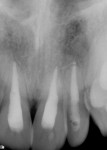

At presentation (Figure 1 through Figure 4), the patient was symptomatic with a dull ache. Teeth Nos. 8 and 9 were repositioned incorrectly, with tooth No. 9 being severely malpositioned. Upon examination, the patient was afebrile and alert and oriented times three. He stated that he did not lose consciousness at the time of the trauma. The patient’s vital signs were determined and considered normal. The patient had no history of significant medical disease, denied all medications, and had no known drug or food allergies. His review of systems was noncontributory for systemic disease. The patient’s head-and-neck examination exhibited no signs of facial fracture. A small laceration of his upper lip in association with tooth No. 9 was healing well. Teeth Nos. 8 and 9 were malpositioned, with tooth No. 9 being severely extruded. The remainder of his head-and-neck examination was unremarkable.

Teeth Nos. 8 and 9 were tender to percussion and palpation. Teeth Nos. 8 and 9 were nonresponsive to cold testing (Frigi-dent™, Ellman International, www.ellman.com). Teeth Nos. 8 and 10 were +1 mobile, while tooth No. 9 was +3 mobile. The gingival tissue around tooth No. 9 was erythematous. Periodontal probing depths were 3 mm to 4 mm generalized for all teeth except tooth No. 9, whose probing depths were 6 mm to 8 mm. Upon radiographic examination, teeth Nos. 8, 9, and 10 had widened periodontal ligament spaces. No other pathology was noted. The remainder of the examination was unremarkable.